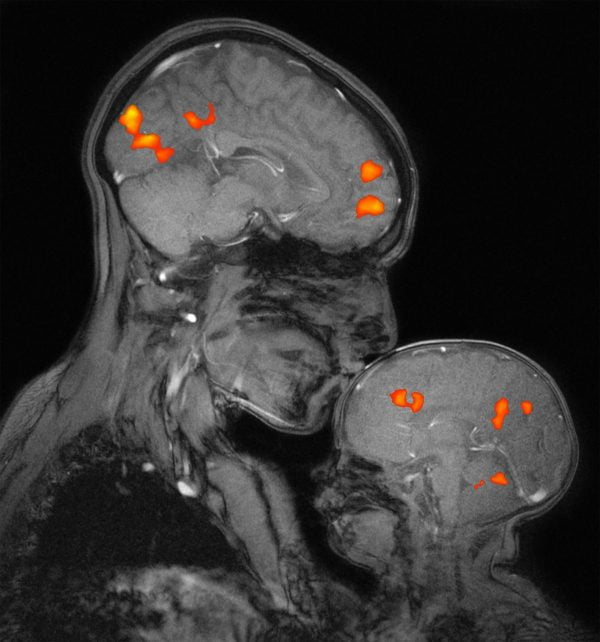

Le atipie precoci del neurosviluppo nello spettro autistico